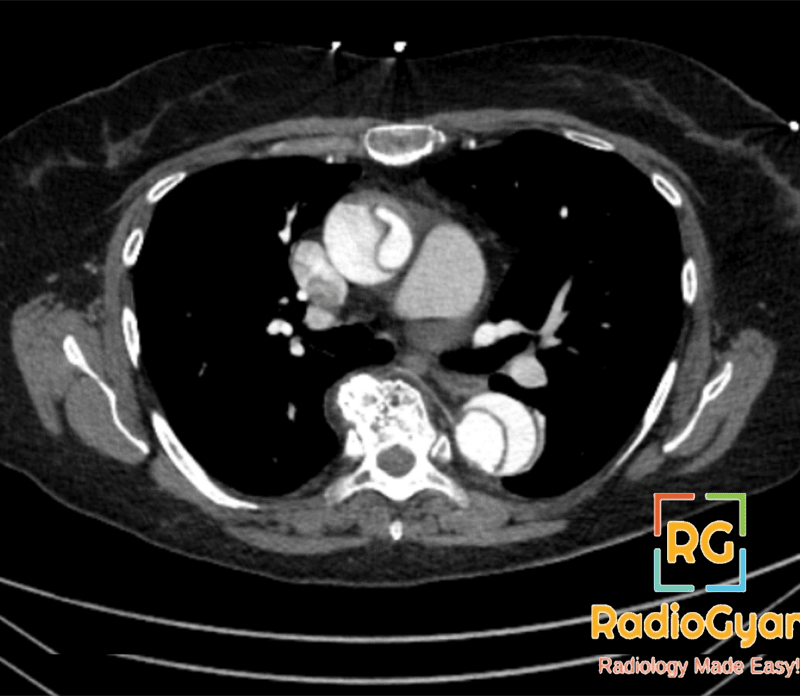

Acute type A aortic dissection (AAD) is a life-threatening emergency that carries a high mortality rate without surgical treatment . Surgical mortality has been estimated to range from 9% to 30%, and survival rates of 51–82% at 5 years have been reported.

상행은 흉부외과 emergent open surgery indication. 바로 상급병원 연락해서 전원.

CXR에서 mediastinal widening, aortic notch를 잘 봐야한다.